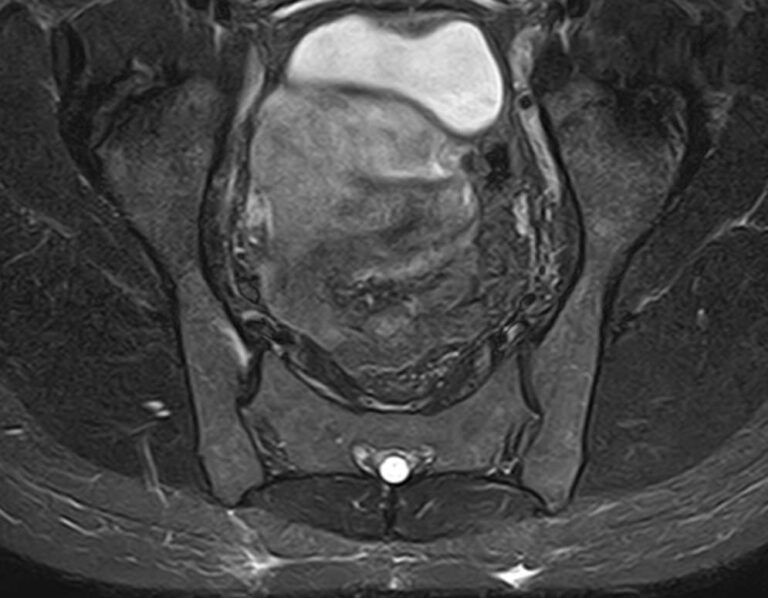

Крестцово-подвздошное сочленение – это крупный малоподвижный сустав, место соединения крестца и подвздошных костей, которое часто вовлекается в патологический процесс при травмах, дегенеративных поражениях, инфекциях и опухолевых заболеваниях.

С помощью МРТ можно диагностировать поражение крестцово-подвздошных сочленений на начальной стадии, когда другие методы не дают результатов. Такой патологией, в частности, является сакроилеит (воспаление крестцово-подвздошного сочленения), который часто становится причиной анкилоза (сращения) или нестабильности (патологической подвижности) сустава. Выявление сакроилеита на ранней стадии значительно улучшает прогноз в плане лечения и профилактики осложнений.

В клинике «Доступная медицина» диагностика патологии крестцово-подвздошных сочленений осуществляется на новейшем высокопольном томографе экспертного уровня TOSHIBA VANTAGE TITAN 1,5 Тесла. Аппарат проводит сканирование в различных плоскостях, делая срезы с шагом от 1 мм, затем с помощью компьютерных программ преобразует полученные данные в трехмерные изображения.

Что показывает МРТ крестцово-подвздошных сочленений

• Повреждения суставно-связочного аппарата в этой области;

• Дегенеративные и воспалительные процессы;

• Метастазы и опухолевые процессы. МРТ крестцово-подвздошных сочленений помогает выявлять новообразования на ранних стадиях, что не под силу многим другим методикам исследования. МРТ крестцово-подвздошного сочленения рекомендуют при наличии следующих жалоб пациента: